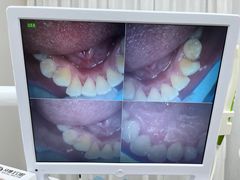

• 牙博士口腔品牌连锁(杨浦店)

• -牙博士口腔品牌连锁(杨浦店)

鱼自乐之 | 22-08-14

旦旦先森 | 22-08-14